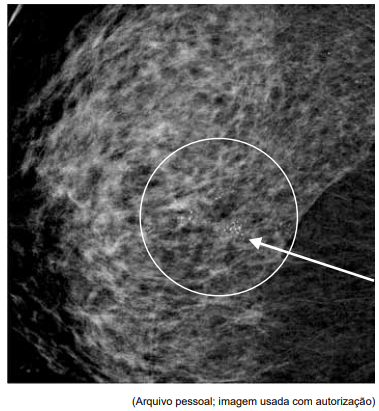

Paciente de 57 anos, assintomática, sem história familiar de câncer de mama, comparece ao serviço de ginecologia trazendo mamografia de rastreamento, reproduzida a seguir. O exame físico não evidencia nódulos palpáveis ou linfadenopatia axilar.

Qual a conduta diagnóstica mais apropriada neste caso e a hipótese histopatológica mais provável, caso se confirme malignidade?